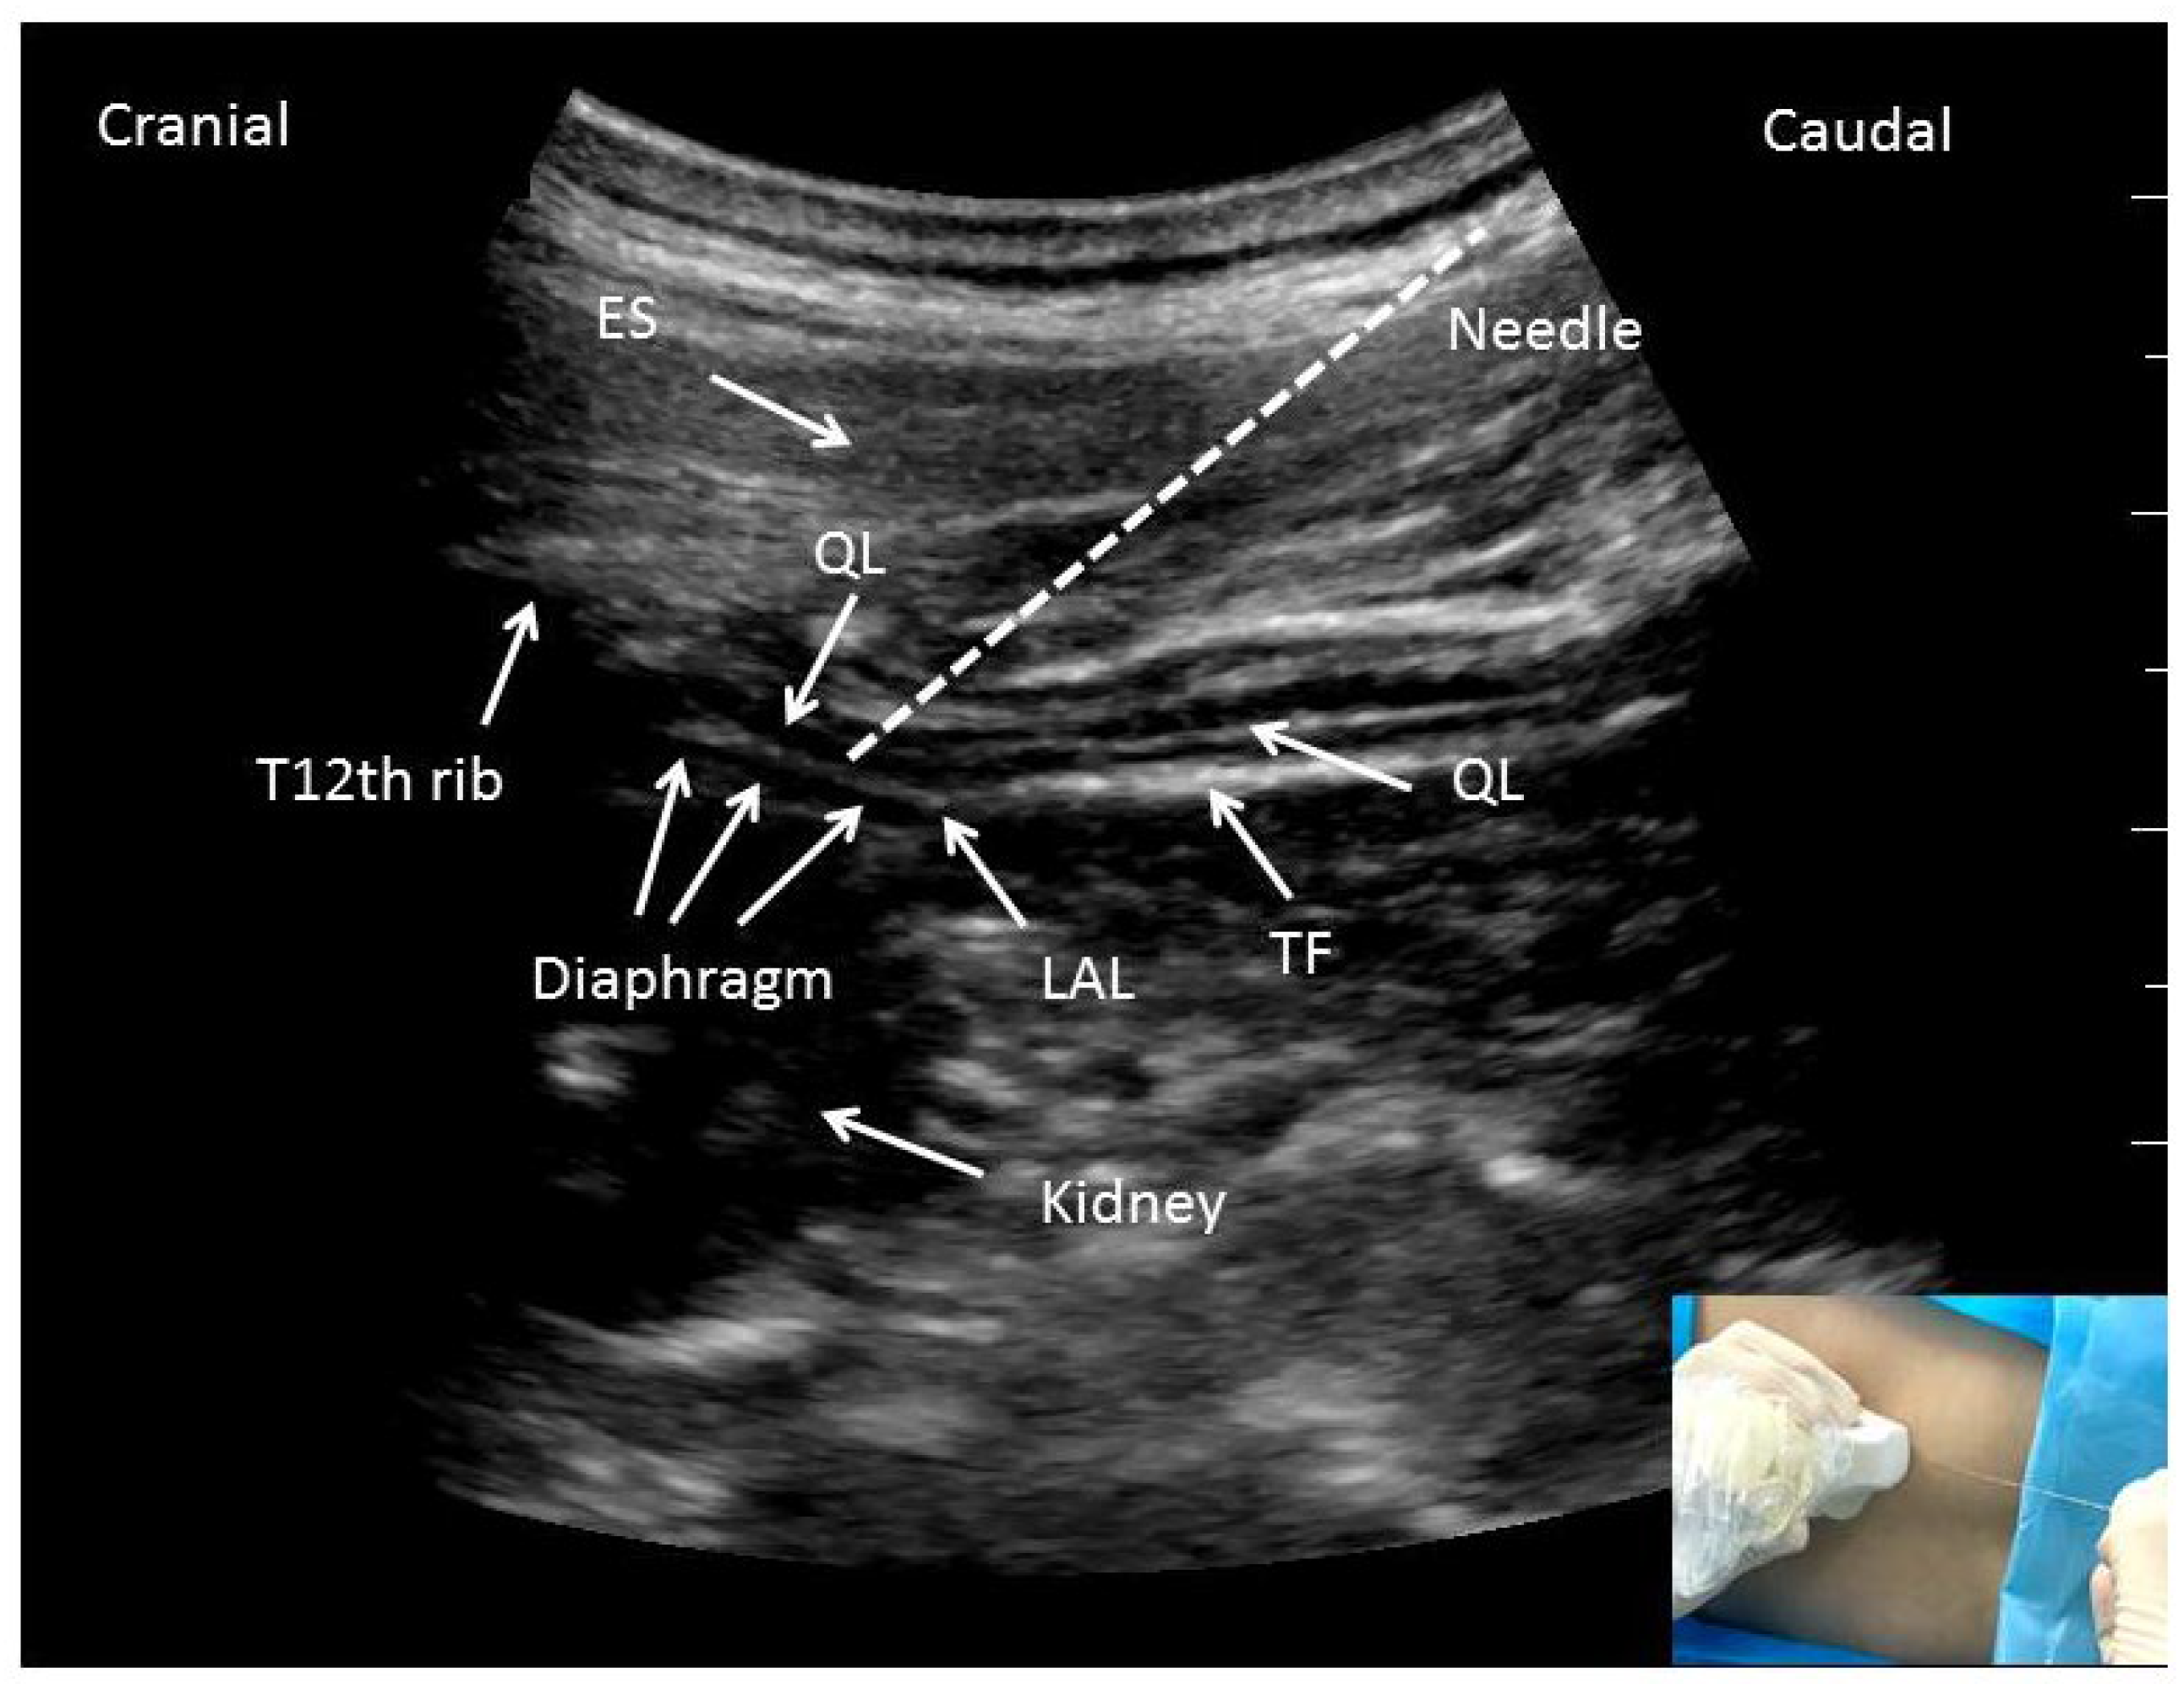

Ultrasoundguided posterior quadratus lumborum (QL) block. ES, erector Ql Block For Cesarean Section several studies have examined the role of tap block as part of a multimodal approach in postoperative analgesia after caesarean section,. the quadratus lumborum block (qlb) is performed in close proximity to the surface and uses a fascial compartment path to. Specific attention will be given. quadratus lumborum block has been shown to provide satisfactory analgesia after. Ql Block For Cesarean Section.